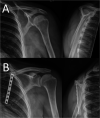

Figure 10.

(A) Pre-operative & (B) post-operative radiographs of patient with left ST demonstrating 8-hole 1/3 tubular plate utilised as ‘washer’.